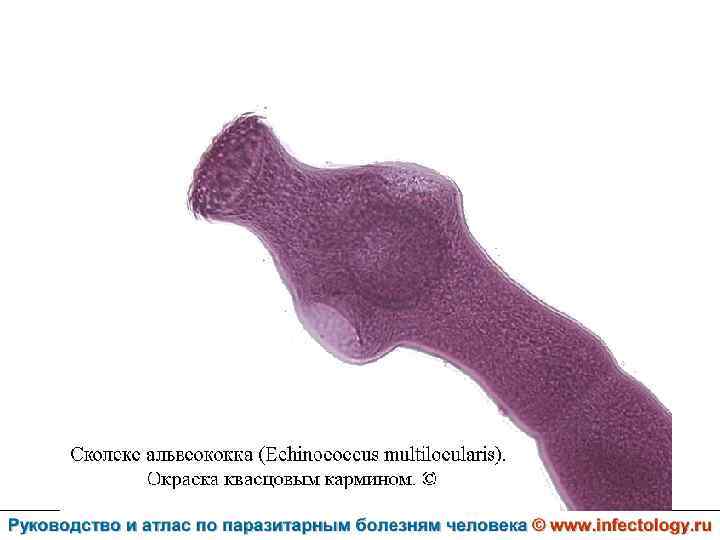

Альвеолярный (многокамерный) эхинококкоз человека (альвеолярный гидатидоз) (шифр по МКБ 10 - B 67. 5 -7) – зоонозный биогельминтоз, характеризующийся чрезвычайно тяжелым хроническим течением, первичным опухолевидным поражением печени, нередко с метастазами в головной мозг и легкие, а также во многие другие органы. Заболевание часто заканчивается летально.